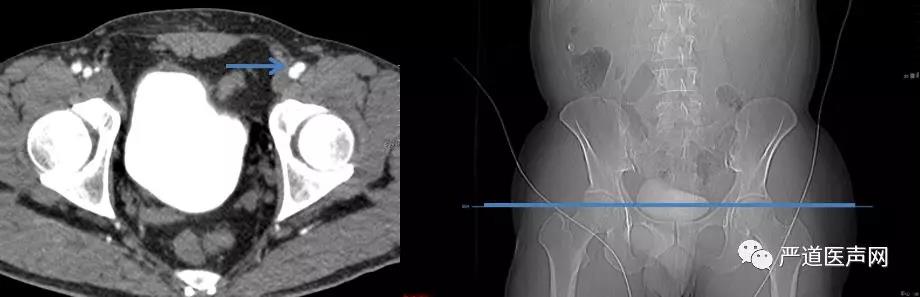

检查双侧股动脉情况确定入路。

经皮穿刺左股总动脉,预置2Proglide缝合器,建立从股动脉至升主动脉通道,穿刺左股静脉并送入临时起搏电极至右室备用。